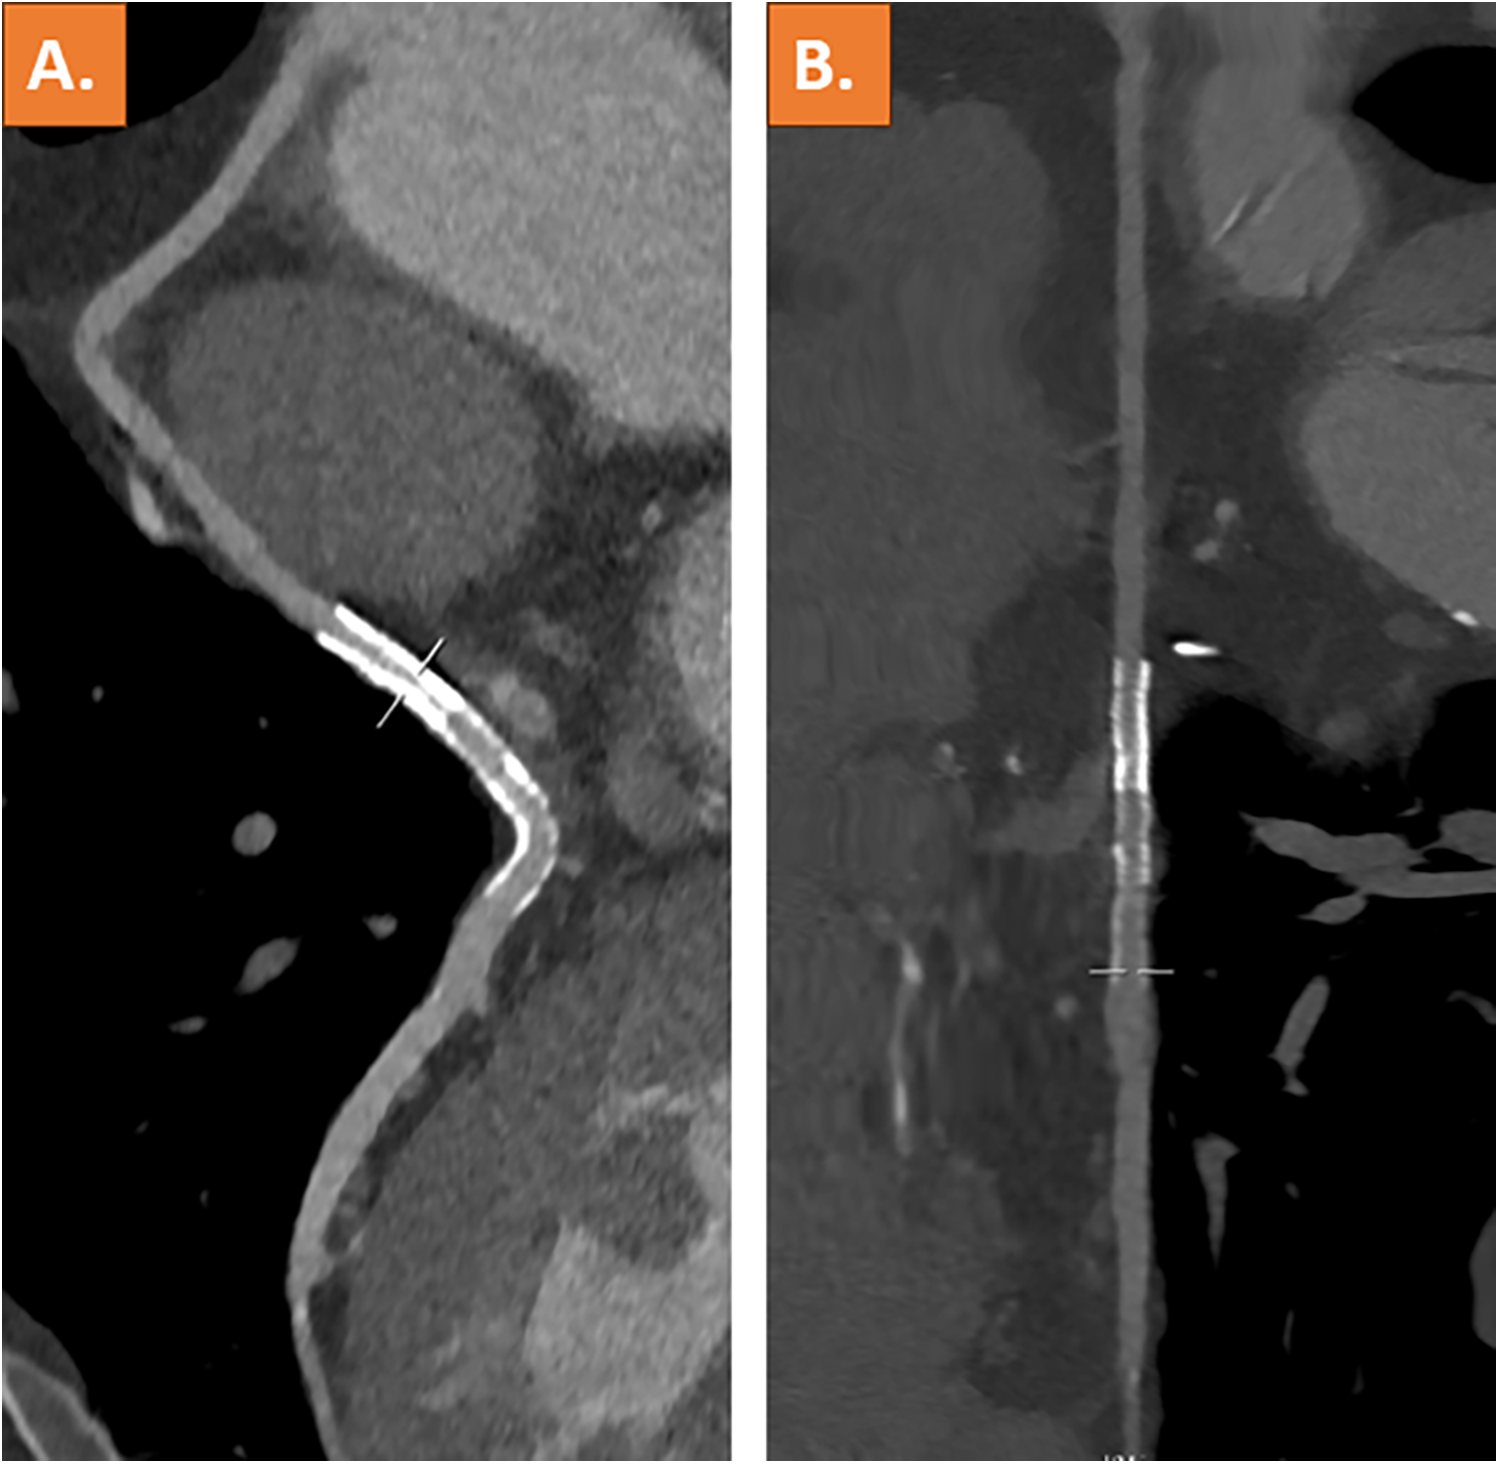

Coronary computed tomography angiography (CCTA), which was performed after 3 days, showed complete resolution of the thrombus and a patent vein graft (Figures 3A,B). The patient was discharged on the following day and remained on treatment with dual platelet inhibition for 12 months.

Figure 3

Coronary computed tomography angiography with curved multiplanar reformation (A) and stretched vessel view (B) showing a patent venous coronary artery bypass graft including stent lumen and complete resolution of the thrombus.